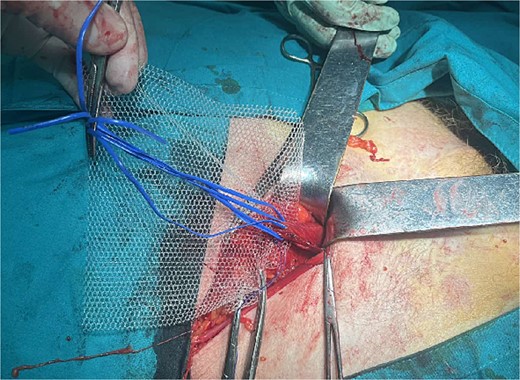

A 72-year-old patient, in good physical condition with a BMI of 26.1, came for an examination due to swelling in the right lateral abdominal wall without swelling of the scrotum. The patient was operated on for a right-sided inguinal hernia as an 8-year-old boy, but there was no appropriate medical documentation for the operative technique used. A month ago, besides the swelling, he experienced occasional abdominal pain and difficulties during physical activities in his garden. During clinical examination, a soft swelling in the right lateral abdominal wall, compressible under palpation was ascertained (Fig. 1). The abdominal ultrasound and contrast abdominal CT showed a thinned right abdominal wall with superficial intestinal loops and the differential diagnosis of a large recurrent inguinal or Spigelian hernia was presumed (Fig. 2). The patient received one dose of prophylactic cephalosporin preoperatively, and was operated on under general endotracheal anesthesia, in a supine position with a lumbar pillow placed for a slight tilt to the left. A right lateral lumbar-inguinal skin incision 4–5 cm above the anterior superior iliac spine in a horizontal direction following the lumbar dermatomal lines was performed. Subcutaneous fat was gently separated and the hernial sac dissection went to its apex below the right costal arch and base to the deep inguinal opening. When the sac was completely freed, the final diagnosis of giant recurrent indirect inguinal hernia (Fig. 3), and the sac with its content was repositioned in the abdominal cavity without opening the abdominal cavity and partial closure of the internal iliac ring was performed with resorptive sutures. After the dissection of the inguinal ligament up to the pubic tubercle (without extending the skin incision) a 15 × 12 cm polypropylene mesh was placed (Fig. 4), fixed to the pubic tuberculum and conjoint tendon with a laparoscopic taker (Fig. 5), and the ileopubic ligament partly with individual and partly with continuous non-absorbable polypropylene 2/0 suture. An opening for the spermatic cord was provided and medially the mesh was fixed with individual resorptive stitches (Fig. 6). The aponeurosis of the external oblique muscle was closed as much as it allowed to be approximated followed by individual subcutaneous and skin stitches (Fig. 7). The operating time was 65 minutes without blood loss and the patient had a quick and satisfactory recovery. He was discharged from the hospital on the third post-op day, and the skin stitches were removed on the 14th day. One month after the surgical treatment the patient was in good condition without any complaints (Fig. 8).

Placement of the polypropylene mesh 15 × 12 cm after dissection of the spermatic cord